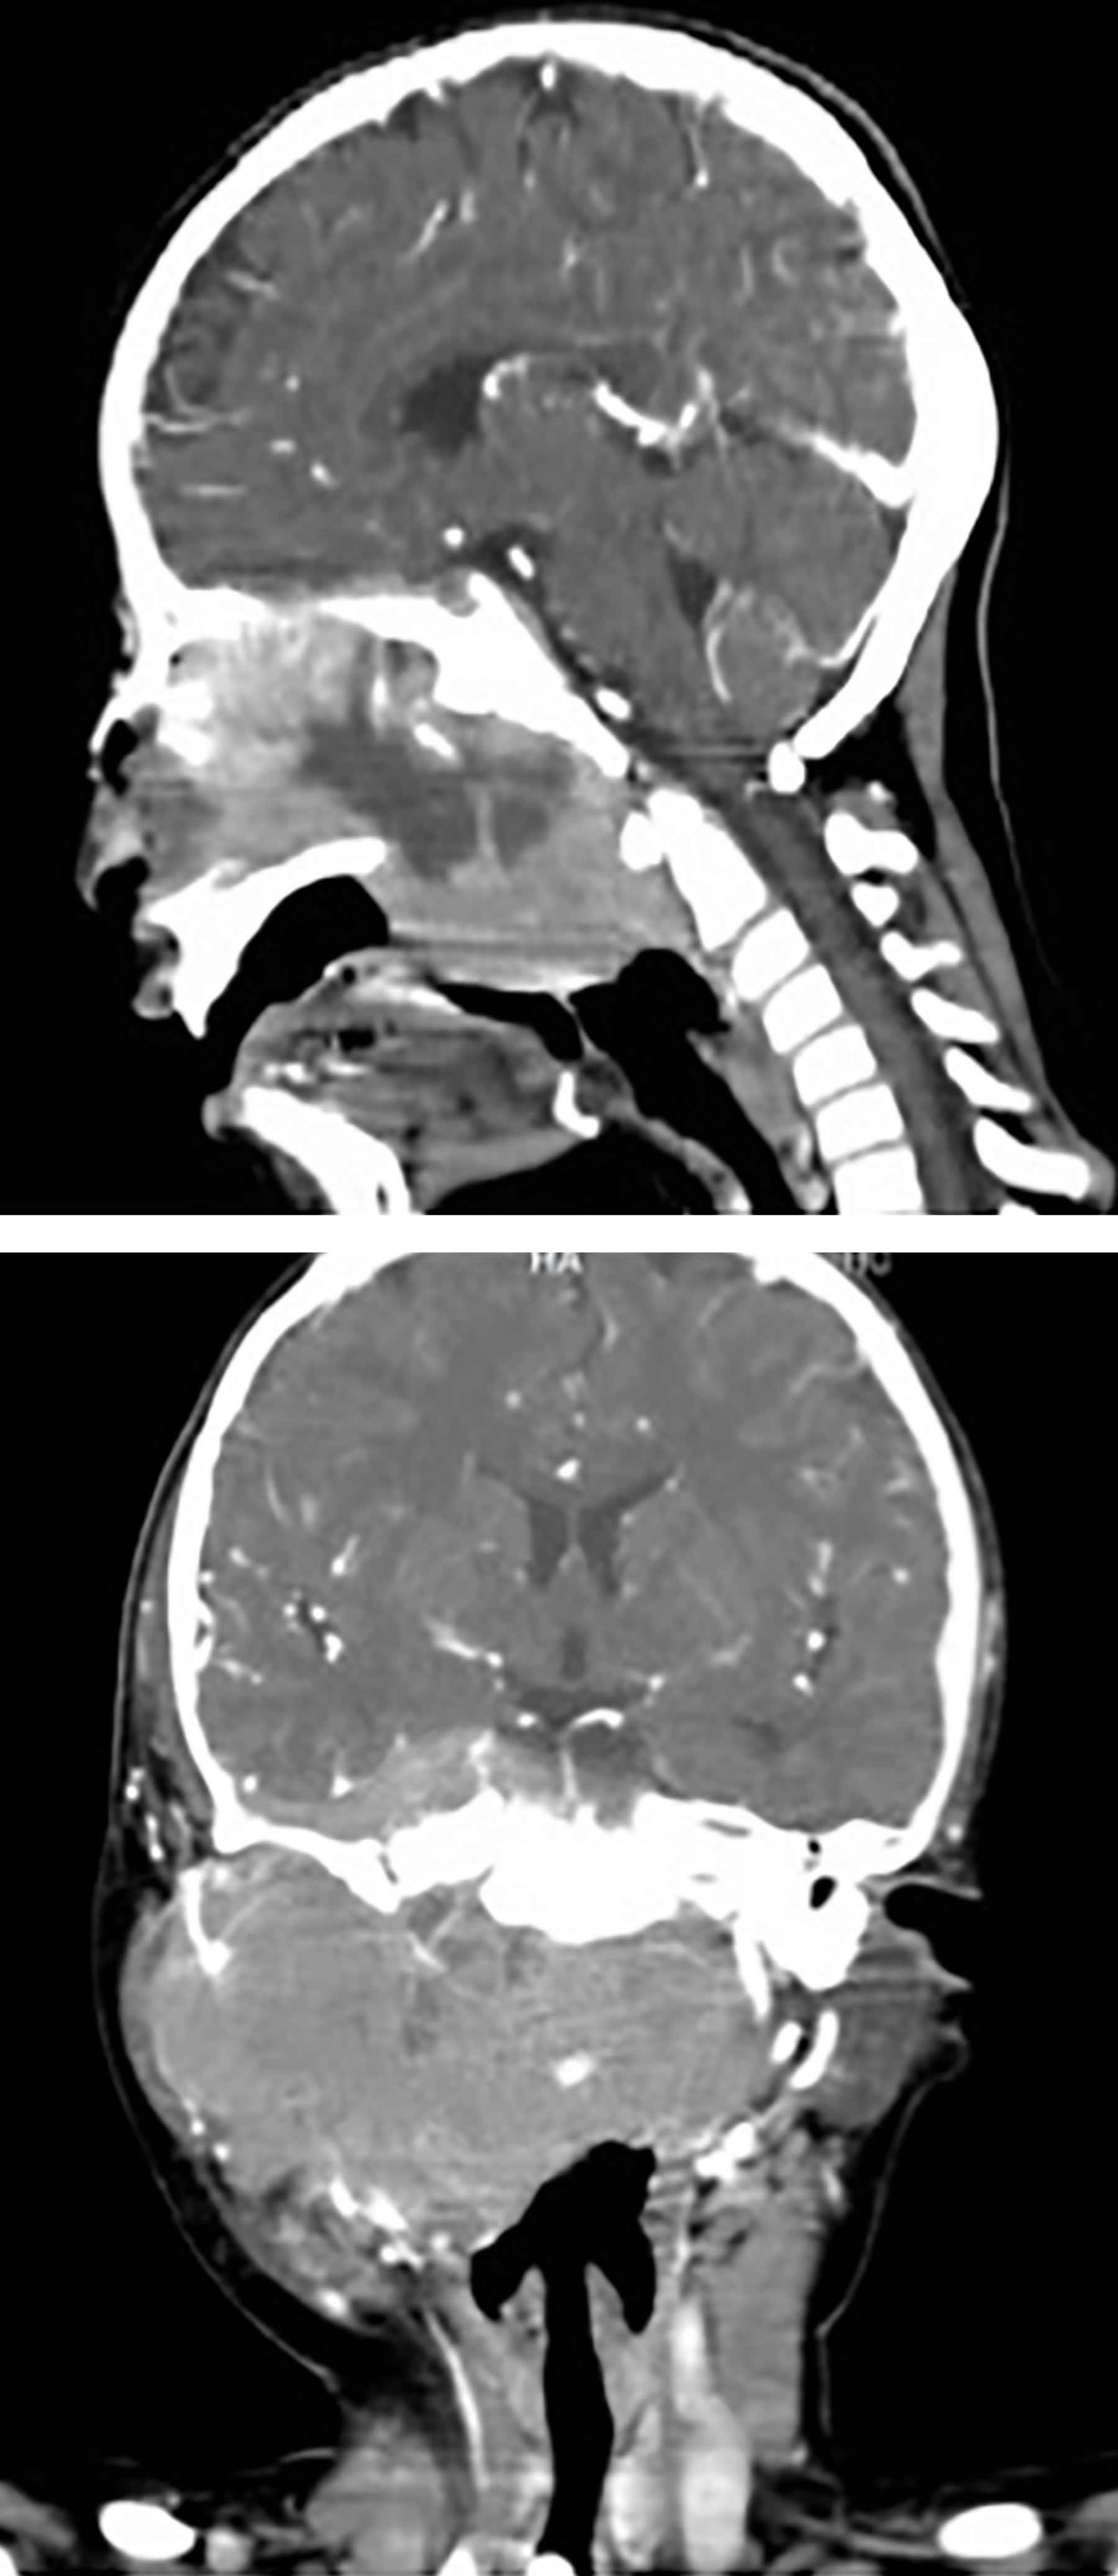

En el mismo mes de junio inició tratamiento con quimioterapia bajo el protocolo FAB LMB-96, que incluye vincristina, prednisona, ciclofosfamida, doxorrubicina, metotrexato, citarabina y etopósido. En julio hubo disminución del volumen tumoral a nivel cervical, el cual ya no era palpable (Figura 7).

Figura 7